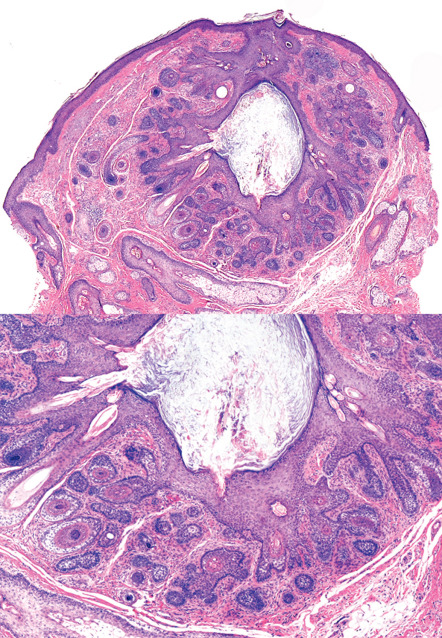

Prototypically, a trichofolliculoma consists of a central cystic space with infundibular cornification and central orthokeratin. Sometimes, cross-sections of hair shafts are identifiable within the cyst. Relatively well-developed and occasionally oddly formed vellus follicles protrude in radial fashion from the central structure ( Fig. 111.3 ). The follicles usually display a bulb and papilla and exhibit inner and outer sheath and isthmic differentiation. The entire structure, including the central cyst and its associated radiating follicles, is enveloped by a vascularized fibrous (angiofibroma-like) stroma.

The radiating follicles are frequently cut on tangent, thus creating considerable microscopic variation, and deeper sections through the tissue block sometimes are required for diagnosis. If the radiating follicles are accompanied by sebaceous glands, the hamartoma can be termed a sebaceous trichofolliculoma . This diagnostic embellishment is not of any clinical import.